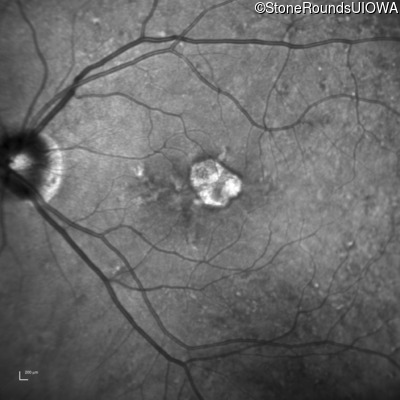

Blue Autofluorescence - Right - 20/25

Exemplar